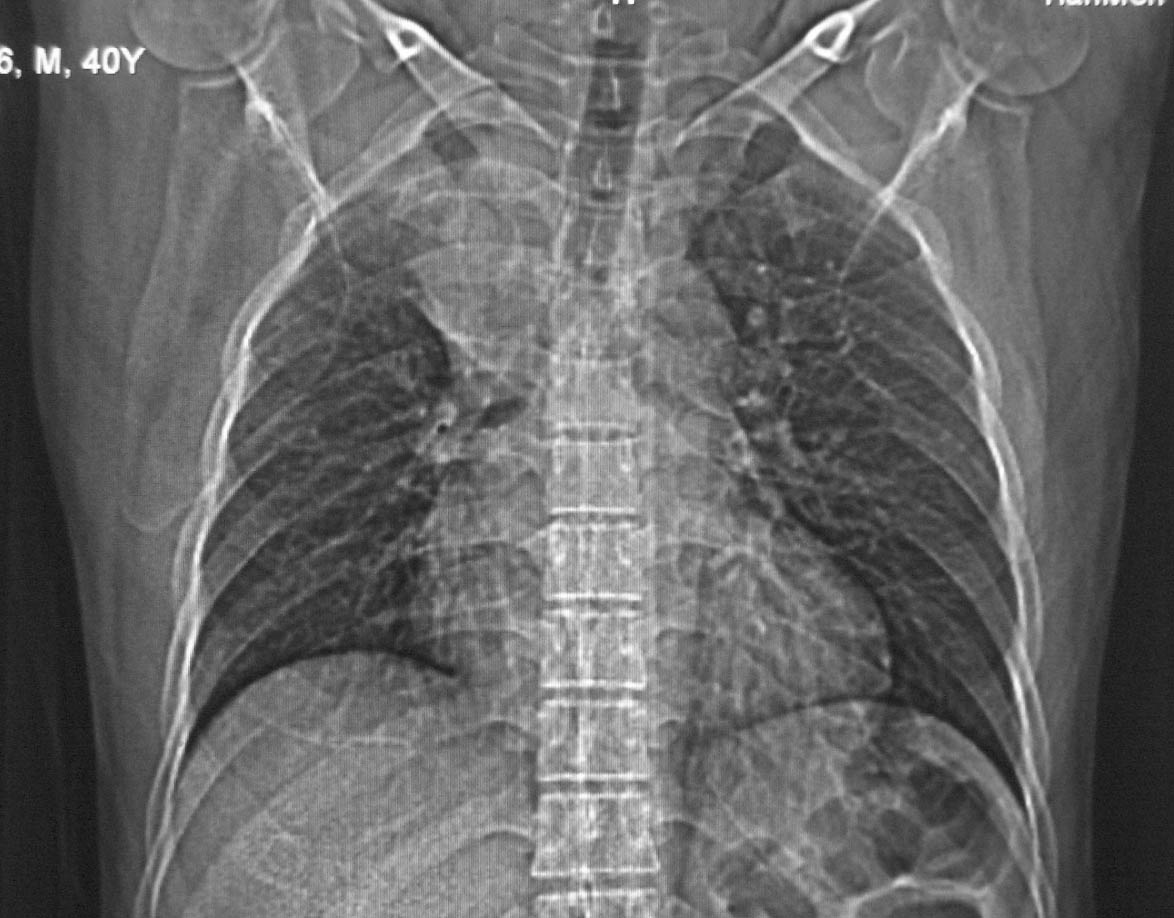

标题: CT5485:[原创]肺部占位请讨论

右上肺ca并肺不张,纵隔淋巴结转移

右肺上叶中央型肺癌并上叶肺不张、纵隔淋巴结肿大

右上叶支气管后壁明显增厚,支持右肺上叶中央型肺癌伴右上叶肺不张、纵隔淋巴结肿大。

左肺上叶不张,可见软组织肿块,左肺上叶支气管狭窄,呈鼠尾征,左侧胸腔内见少许积液,纵隔内未见肿大淋巴结,建义做个增强或支气管镜

考虑右上肺癌并肺不张,纵隔淋巴结转移

右上叶支气管后壁明显增厚,支持右肺上叶中央型肺癌伴右上叶肺不张、纵隔淋巴结肿大。建议支气管镜检查。

右肺上沟癌、局部肺段不张,纵隔淋巴结肿大

右上叶支气管肺癌并右上叶阻塞性不张,右侧少量胸腔积液.

右上肺中央性肺癌伴右侧胸腔少量积液!右上肺胸膜下还有一小病灶,不完全排除结核,但个人支持恶性肿瘤!建议早穿刺活检。

右上叶支气管开口变窄,纵隔见肿大的淋巴结。支持右上叶中心型肺癌并右上叶不张纵隔淋巴结肿大。

右肺上叶中央型肺癌并上叶肺不张、纵隔淋巴结肿大.右侧少量胸腔积液。

右上肺中心型肺癌并肺不张,纵膈淋巴结肿大。右侧少量胸腔积液。

右肺上叶支气管后壁增厚,呈鼠尾状狭窄,纵隔内未见明显增大的淋巴结影,考虑为中央型肺癌伴右上肺不张

右肺上叶不张,考虑中央型肺癌。右侧胸膜肥厚

右肺上叶中央型肺癌并阻塞性炎症、阻塞性肺不张……

右上肺癌,肺不张,纵隔淋巴结肿大

右肺上叶中央型肺癌